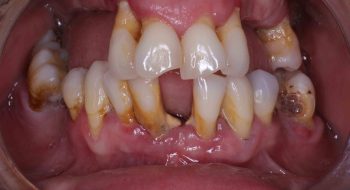

Tooth implant procedure (Dental implant procedure)?

Tooth implant surgery is a procedure that replaces missing tooth or damaged tooth with screw like bio-compatible material called titanium or zirconium. The damaged tooth is removed and the tooth implant is placed in the jaw bone under anaesthesia by an implantologist. Once the tooth implant is placed in the jaw bone, it is allowed to heal and osseointegrate (fuse with the surrounding bone) to become part of the human body. After 4-6 months’ time, the crown is placed on the implant to restore the functionality of the tooth.